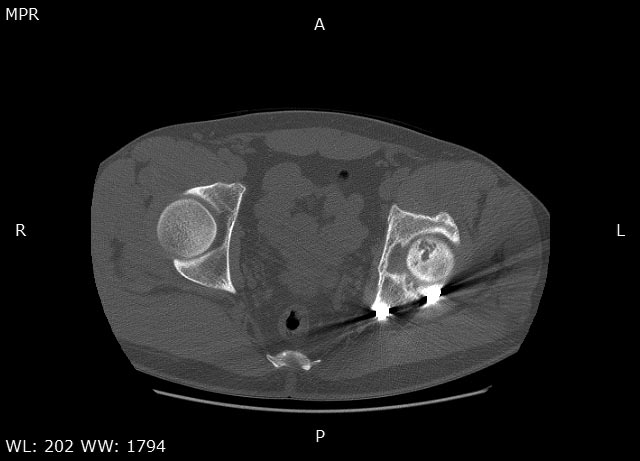

Травма в 2015 году. Водитель, попал в ДТП. Первично повреждение печени, перелом локтевой кости слева. Перелом задней колонный и задней стены левой вертлужной впадины. По экстренным показаниям выполнялась лапаротомия. Синтез задней колонны и задней стены через 13 дней через доступ Кохера-Лангенбека. Гладкий послеоперационный период. Выписан на амбулаторное лечение через 15 дней после операции. После выписки к нам не обращался, так как является жителем другого региона. Обратился через 2,5 года с жалобами на боли в области левого тазобедренного сустава.

На РКТ таза - перелом сросся. Отмечается кисты в области верхнего полюса головки бедра. Пластина фиксирующая задний край соприкасается с задними отделами головки бедра (видимо произошел частичный лизис костного края).

У пациента посттравматический коксартроз 2ст. Учитывая невыраженный болевой синдром лучше ограничиться удалением металлоконструкции. Головка не деформирована кисты относительно небольшого размера - продолжить консервативное лечение с ограничением нагрузок занятий спортом. Упражнения для сохранения мышц и объема движений, бассейн.